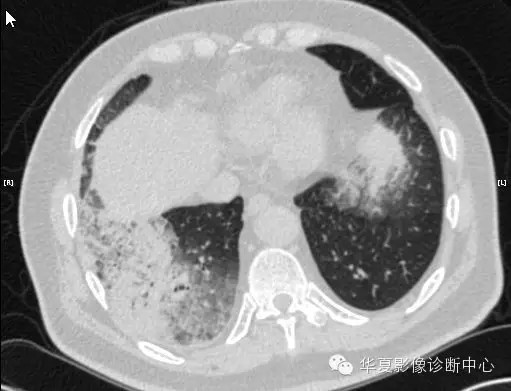

【病例学习】甲型H7N9禽流感一例

男性 63

发热咳嗽5天

2013-4-5拍片示右肺实变,收入院,追问病史,发病期间肌肉酸痛,头痛,无腹痛腹泻,无明显胸闷气急,无意识改变。有高血压病史,无其它病史。

2013-4-7CT进一步检查。

最终诊断:H7N9。